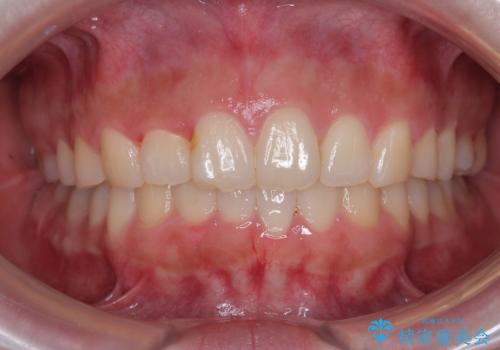

- 上の前歯の隙間を気にして来院された患者様です。

インビザラインにより、上下の歯列を側方に拡大しつつ、前歯の隙間を閉じていくこととしました。

1日22時間の装着時間をしっかりと守ってくださったので、隙間がきれいに閉じ、口元の突出感も改善することができました。